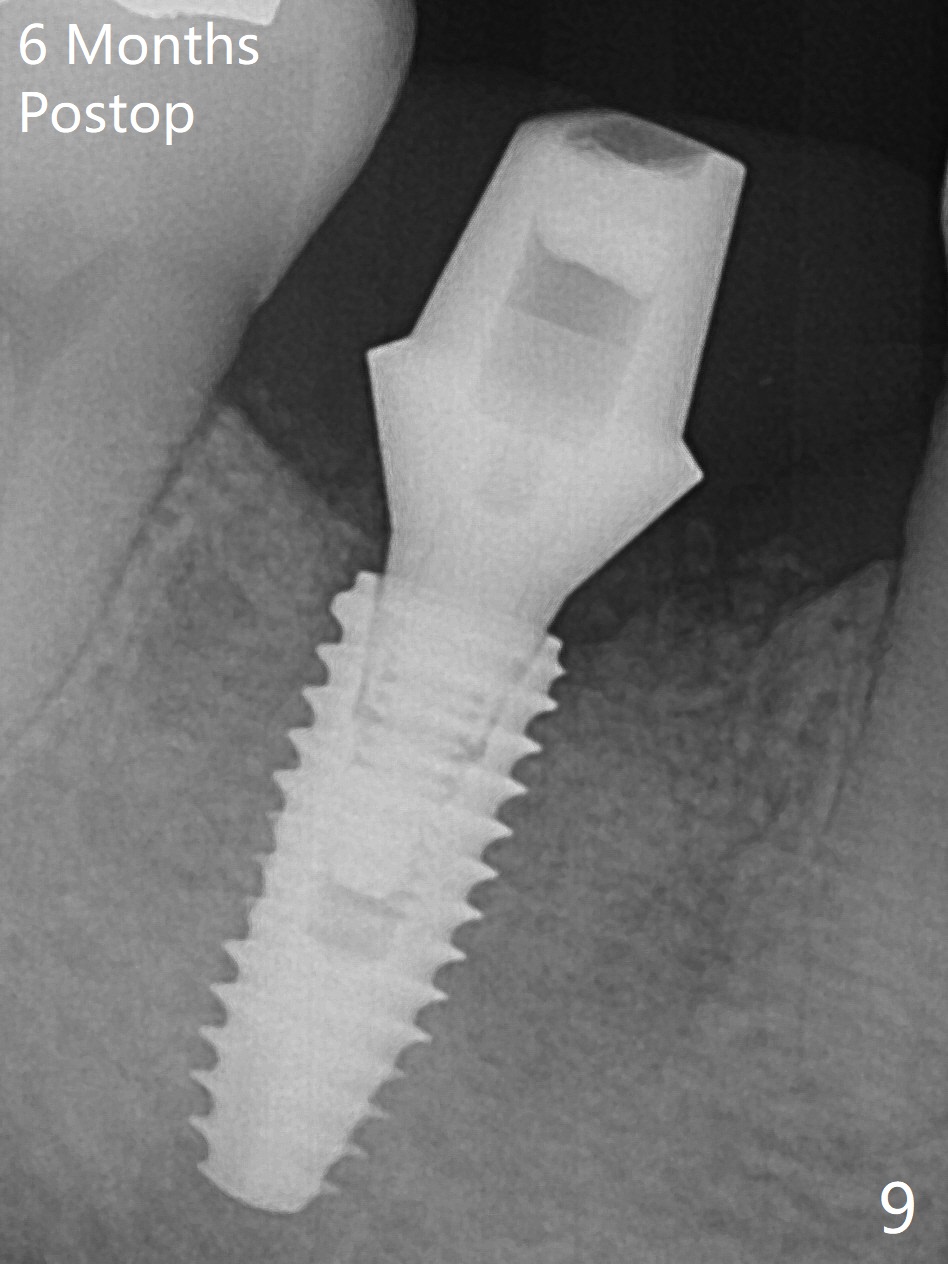

After extraction of the tooth #30, the mesiobuccal plate is found to be lost, corresponding to the fistula (Fig.1 <). Osteotomy is initiated in the flattened septum (lingual) for 13 mm (Fig.2). The patient feels pain when larger drills are being used. Marcaine has to be injected in an infiltration manner for pain control. When a 4.5x10 mm dummy implant is inserted with 55 Ncm, the end of the osteotomy (Fig.3 white line) is close to the Inferior Alveolar Canal (red dashed line). When a definitive implant (Fig.4: 4.5x11.5 mm) is placed with primary stability, there is an apical space (Fig.5 white double arrows). There is moderate postop pain. A shorter implant (10 mm) should be tried when the bone is dense. It will be associated with less pain. The fistula disappears 7 days postop (Fig.6). Although the patient appreciates that the pain is gone, there is atrophy mesiobuccally 2 months postop (Fig.7 *). The implant seems to be have been placed too buccally (Fig.8). With loss of the buccal plate, the implant should be placed away from it to prevent periimplantitis. The abutment is changed from 6.5x4(4) to 6.5x5.5 (3) mm with fabrication of a new provisional. The buccal margin is still supragingival 6 months postop and prep lower before impression. The mesial and distal sockets appear to have healed (Fig.9). When the crown is cemented, the mesiobuccal papilla is present (Fig.10 *), while the mesiolingual one is apparently absent (Fig.11 *). Using a temporary abutment and relining the provisional multiple times would increase the chance of rebuilding the missing papilla. The bone density around the implant increases 11 months post cementation (Fig.12). The dense (apparently cortical) bone seem to grow over the implant plateau 11 months post cementation (Fig.13 <).